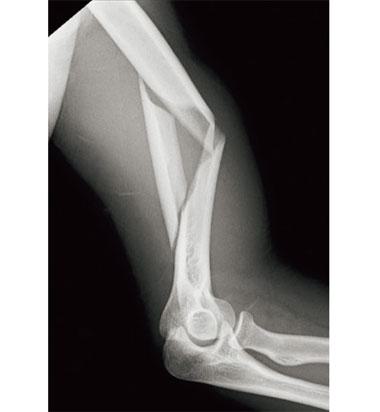

引き寄せ締結法(tension band wiring)により手術直後から骨折部の運動が開始できるのはどれか。

肘頭骨折